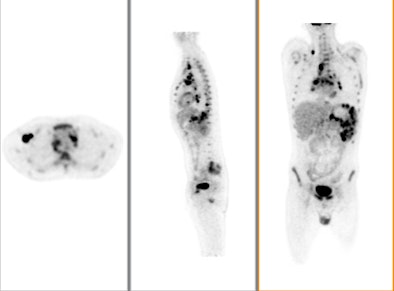

![]() |

| The color PET images are overlaid on a CT scan to show the exact location and extent of disease. The image is from GE Healthcare's Discovery PET/CT 600. Image courtesy of GE and the Cancer Treatment Center of America of Tulsa, OK. |